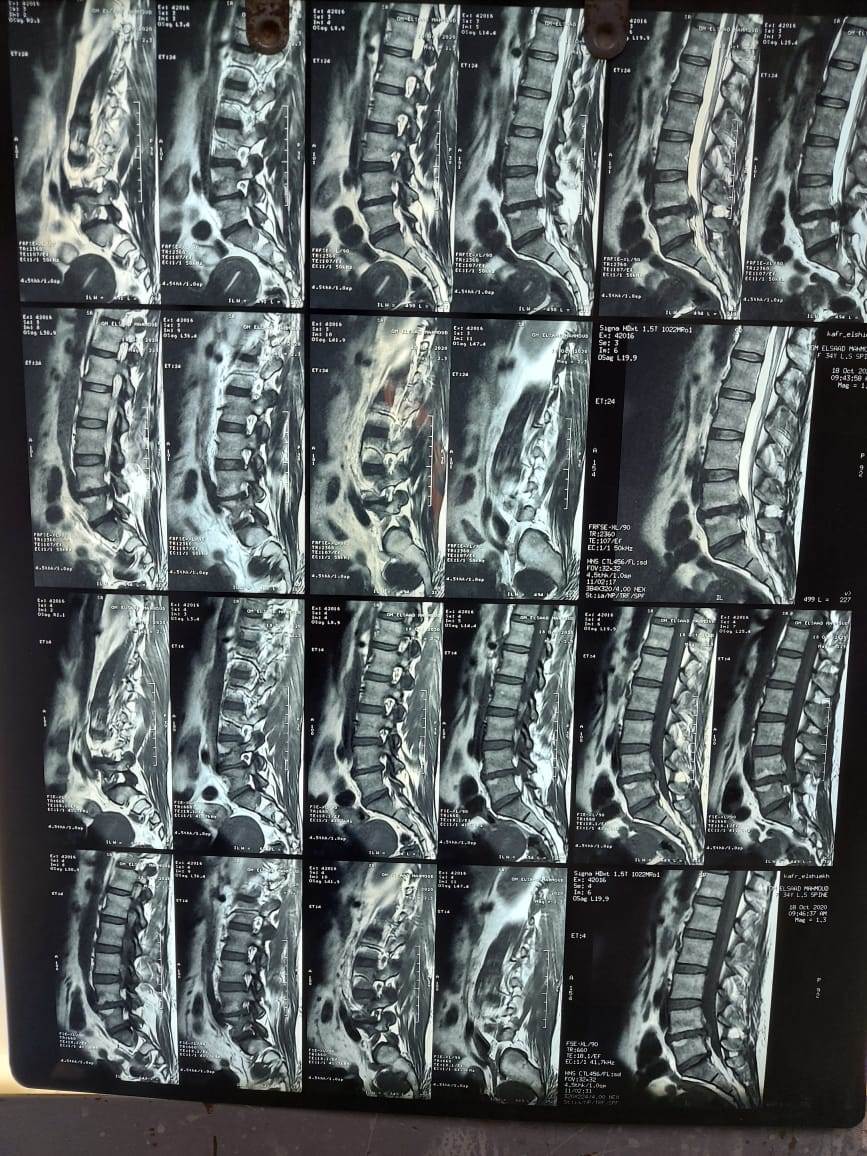

استحدث مستشفى المنيرة العام، خدمات طبية وجراحات جديدة، ولأول مرة أجريت فيه جراحة عمود فقرى، لمريضة تعاني من آلام مزمنة أسفل الظهر، ومنذ 3 أشهر زادت بطريقة شديدة، وتم فحص المريضة وعمل الأشعات اللازمة للتشخيص، وتشخصت بأنها حالة انزلاق فقارى قطني، بين الفقرات القطنية الرابعة والخامسة، والأولى العجزية، وهناك ضاغط علي جذور الأعصاب.

وعلى الفور تم استخراج قرار علاج علي نفقة الدولة، وإجراء جراحة توسيع للقناة العصبية، ومخارج جذور الأعصاب، وتثبيت للفقرات بواسطة أعمدة ومسامير، ودمج للفقرات بواسطة رقعة عظمية ذاتية، وقفص كربوني بين الفقرات القطنية الرابعة والخامسة، واستمرت الجراحة 3 ساعات.